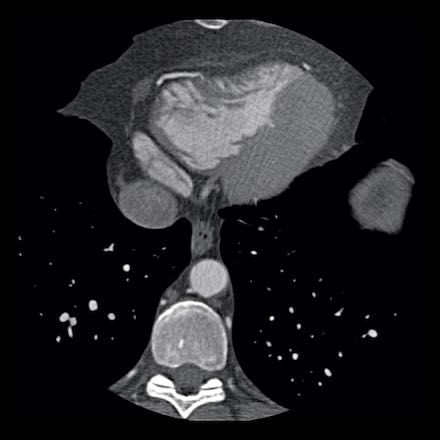

case 3 – Calcium score 0 and severe stenoses.

First, scroll through the CTA images.

How would you describe the findings on the coronary CTA?

The findings are:

- The total calcium

score of 0 indicates the absence of calcified plaque in the coronary

tree. - Severe stenosis

(70-99%) in the mid LAD and D2 branch.